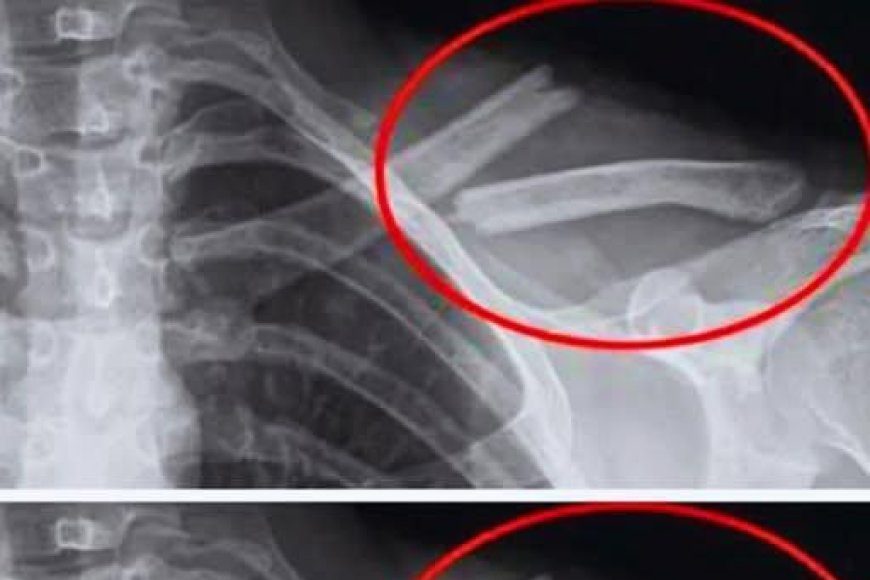

Studien zeigen, dass übermäßiger Limonadenkonsum mit einer Verringerung der Knochendichte einhergeht, insbesondere bei Frauen. Mit anderen Worten: Ihre Knochen werden brüchiger … manchmal ohne jegliche Symptome, bis es zu einem Bruch kommt.

Eine US-Studie mit 2.500 Frauen ergab, dass diejenigen, die regelmäßig Cola konsumierten, eine geringere Knochendichte in den Hüften hatten. Und dies, ohne dass man sich dessen bewusst ist.

Eine an heranwachsenden Mädchen durchgeführte Studie hat außerdem einen Zusammenhang zwischen dem Konsum von Limonade und einem erhöhten Risiko für Knochenbrüche gezeigt.